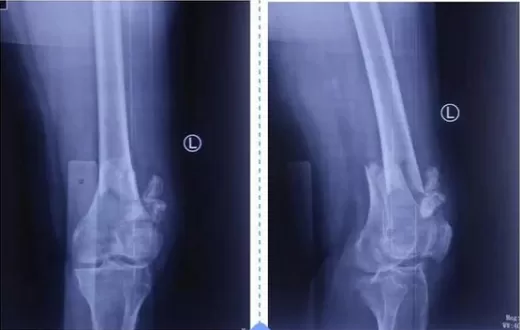

协和江南医院利用3D打印技术,成功为胫骨骨折患者实施手术